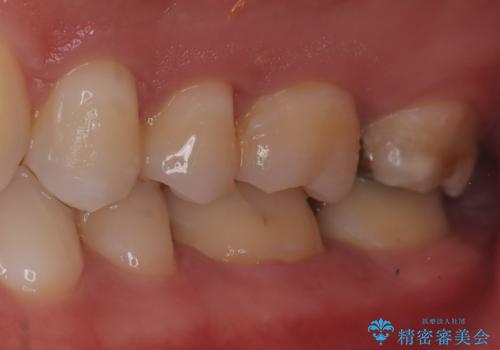

【セラミックインレー】歯科検診にて虫歯発見。

- 定期健診にて虫歯を見つけたためセラミックインレーにて修復しました。

綺麗に仕上がり患者さんも非常に満足されていました。